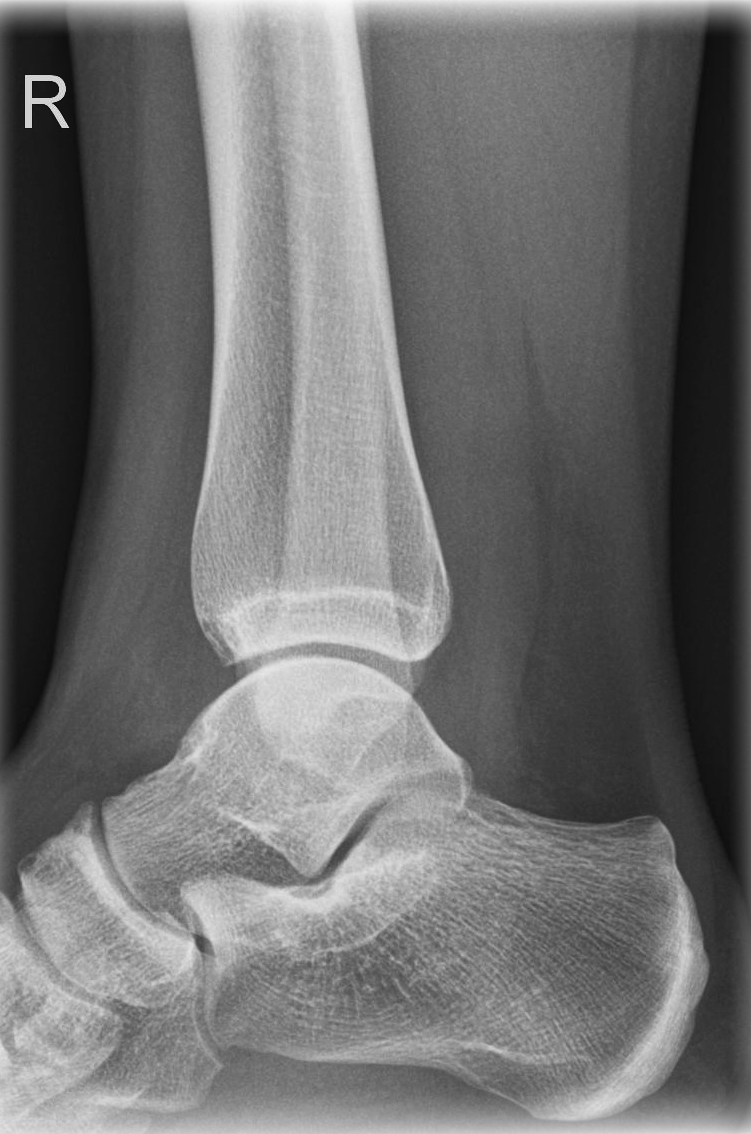

Oberes Sprunggelenk a.-p. (1. Ebene)

Technik

• FDA: 1,05 m

• Ausgangsformat: 18/24

• Übertischaufnahme

Indikation

Fraktur, Bandverletzungen, Luxation

Lagerung

sitzend/ liegend auf Tisch

gestreckte Bein nach innen rotieren, sodass Malleolus medialis und lateralis auf einer Höhe sind

(ca. 15-20° - Zeigefingertest)

Fuß anziehen, möglichst senkrecht zum Unterschenkel

Zentralstrahl

senkrecht

Querzentrierung: Gelenkspalt

Längszentrierung auf Objektmitte

Einblendung

proximal 5 QF ab ZS, lateral 1 QF

Qualitätskriterien

Frei einsehbares oberes Sprunggelenk, insbesondere im Bereich von Innen- und Außenknöchel und der tibiofibularen Syndesmose.